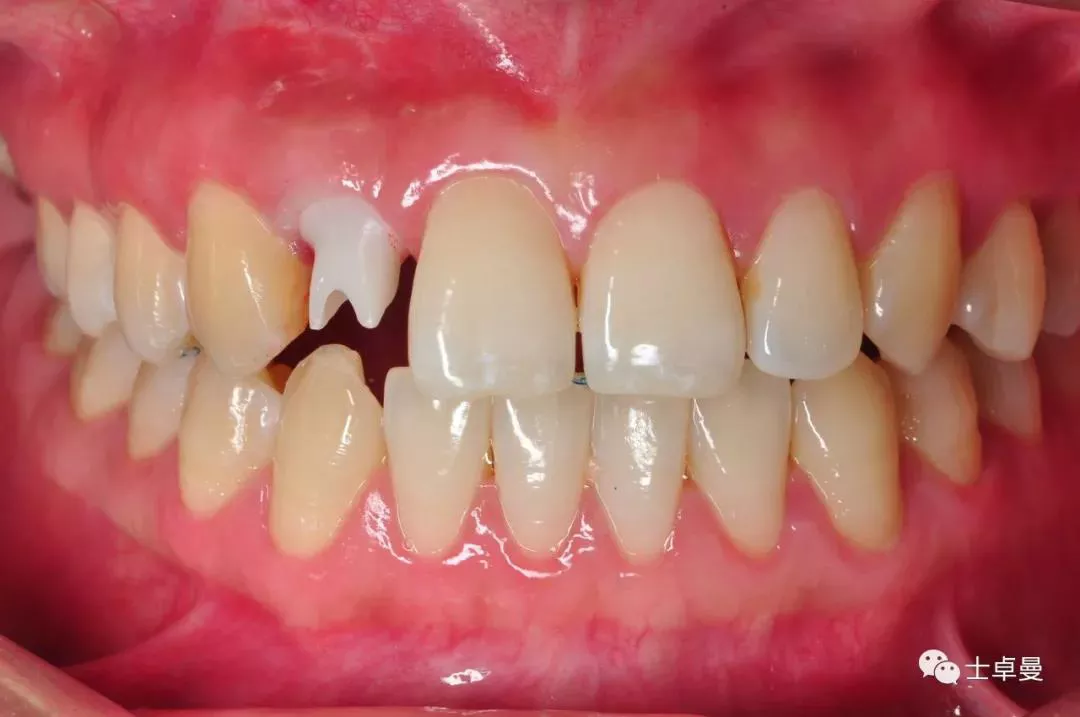

·       10天后拆线,临时义齿稳定,牙龈愈合良好;

拆线时愈合情况

一个月复查